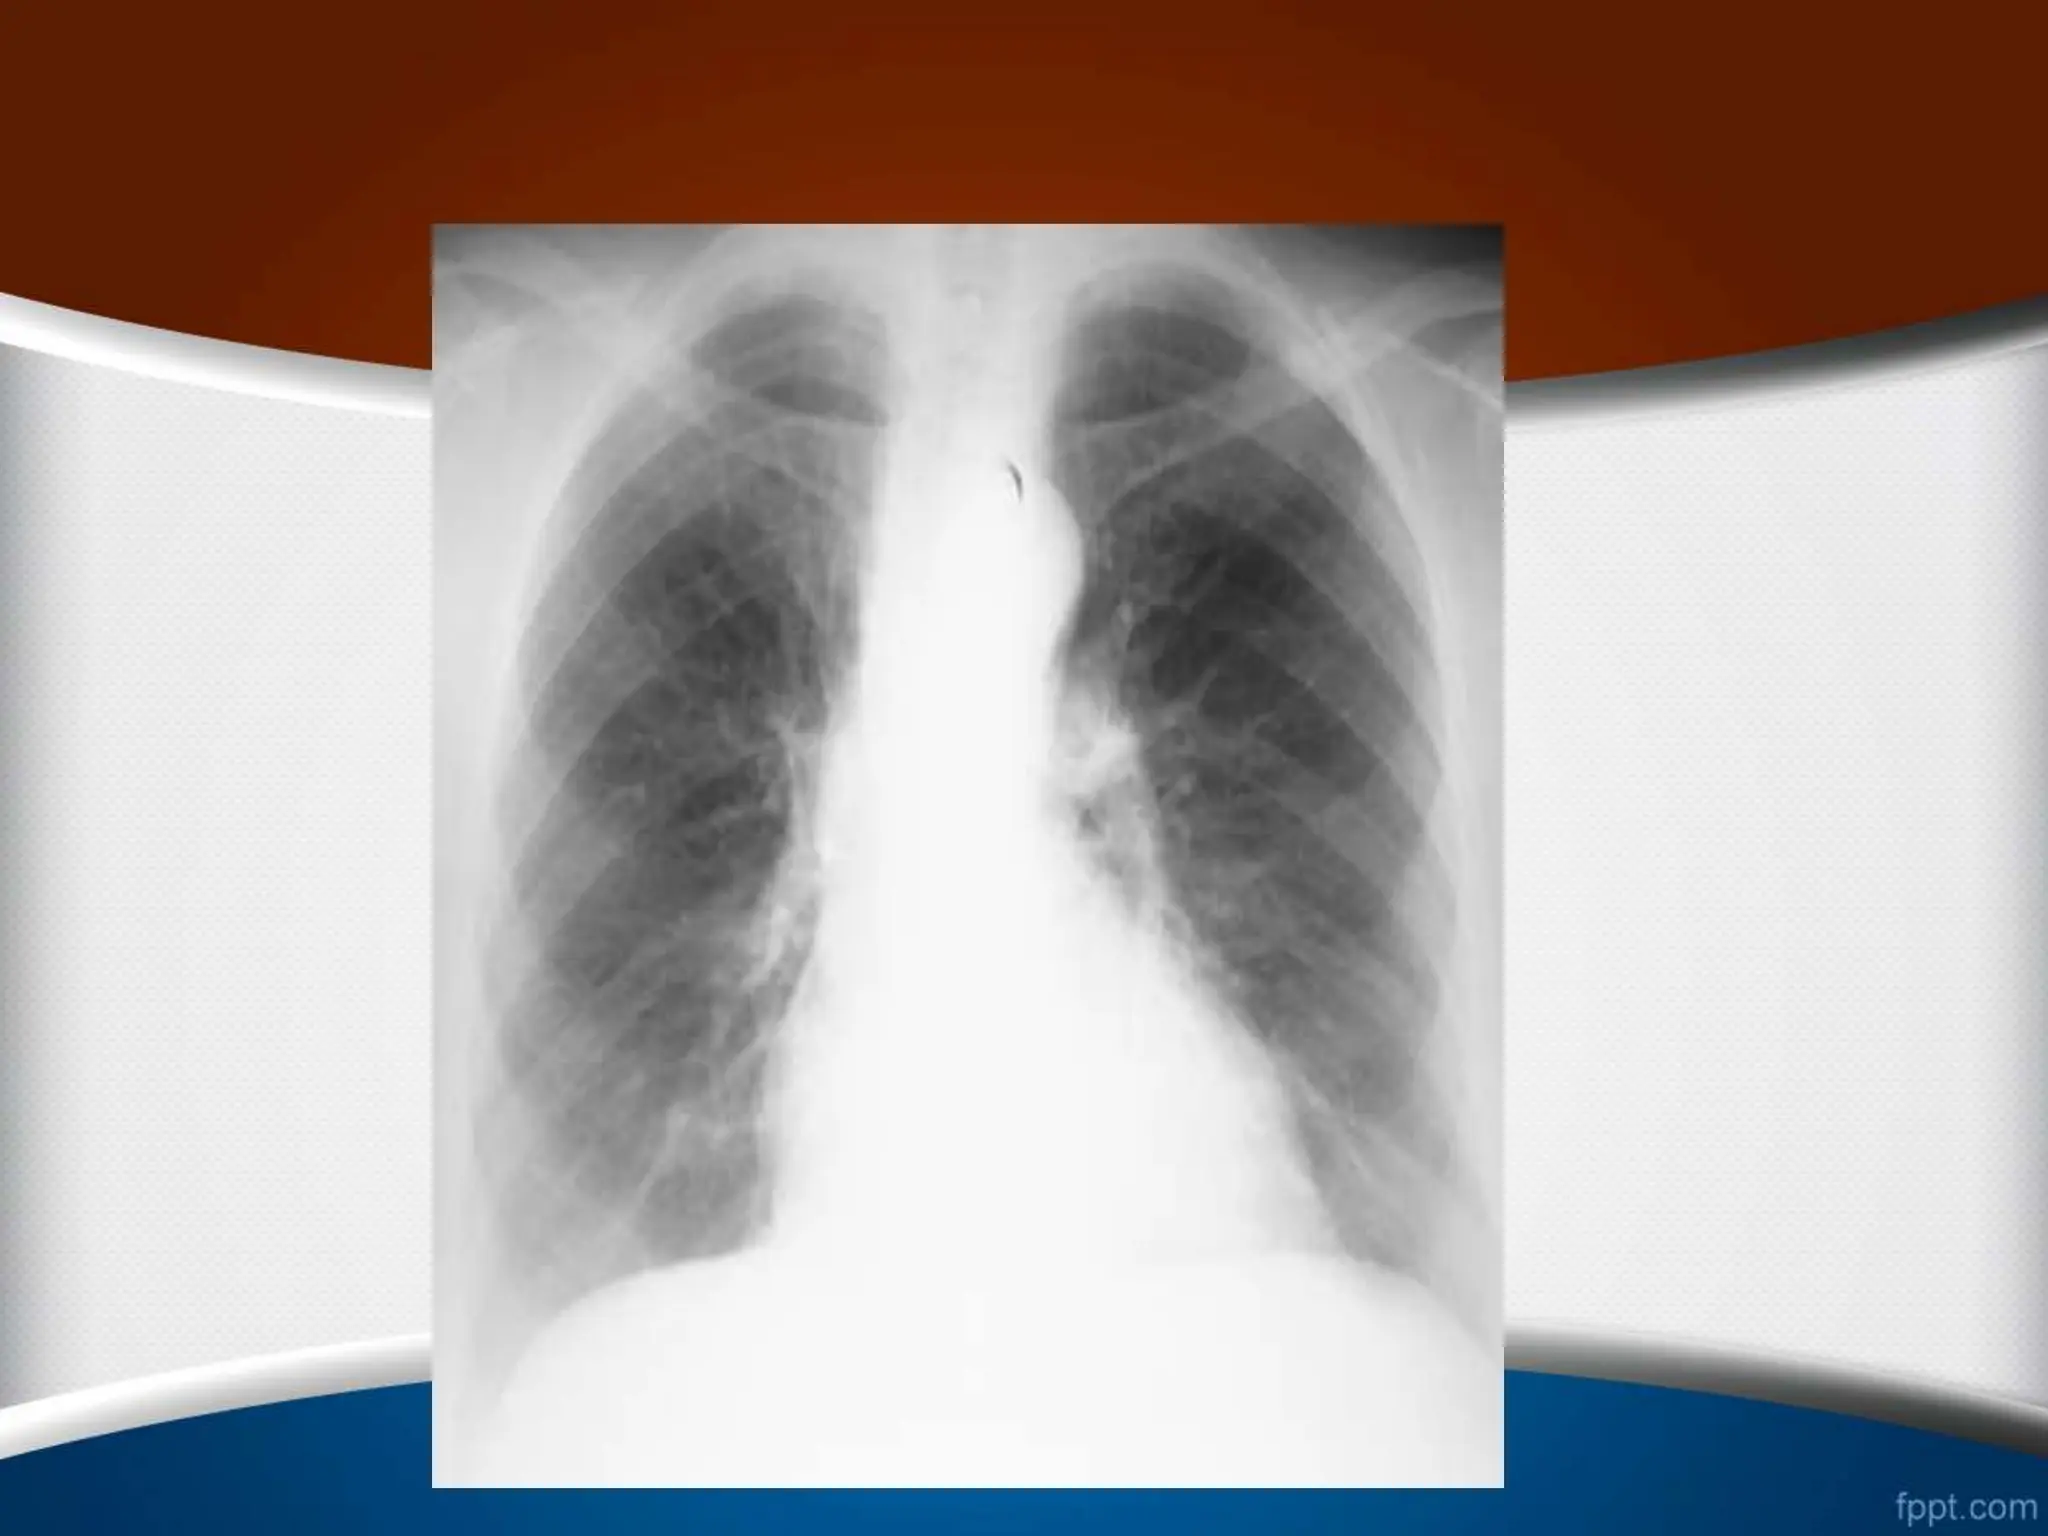

Over exposure

•

1

-

‫مهره‬ ‫بین‬ ‫فضاهای‬

‫می‬ ‫دیده‬ ‫وضوح‬ ‫به‬ ‫ها‬

‫شود‬

.

2

CXR

‫می‬ ‫نظر‬ ‫به‬ ‫تر‬ ‫سیاه‬

‫رسد‬

3

‫می‬ ‫محو‬ ‫عروقی‬ ‫مارکرهای‬

4

‫تفسیرمی‬ ‫خون‬ ‫کم‬ ‫غلط‬ ‫به‬ ‫ریه‬

Under exposure

‫دنده‬

‫مهره‬ ‫و‬ ‫ها‬

‫نمی‬ ‫رؤیت‬ ‫پشت‬ ‫از‬ ‫ها‬

‫می‬ ‫نظر‬ ‫به‬ ‫سفیدتر‬

‫ریه‬ ‫قواعد‬ ‫در‬ ‫کاذب‬ ‫کدورت‬ ‫یک‬ ‫ایجاد‬

‫محو‬ ‫به‬ ‫منجر‬ ‫که‬ ‫ها‬

‫می‬ ‫دیافراگم‬ ‫شدن‬

‫ری‬ ‫اشتباه‬ ‫به‬ ‫است‬ ‫ممکن‬ ‫که‬ ‫عروقی‬ ‫مارکرهای‬ ‫افزایش‬

‫ه‬

‫شود‬ ‫تفسیر‬ ‫خون‬ ‫پر‬ ‫ها‬